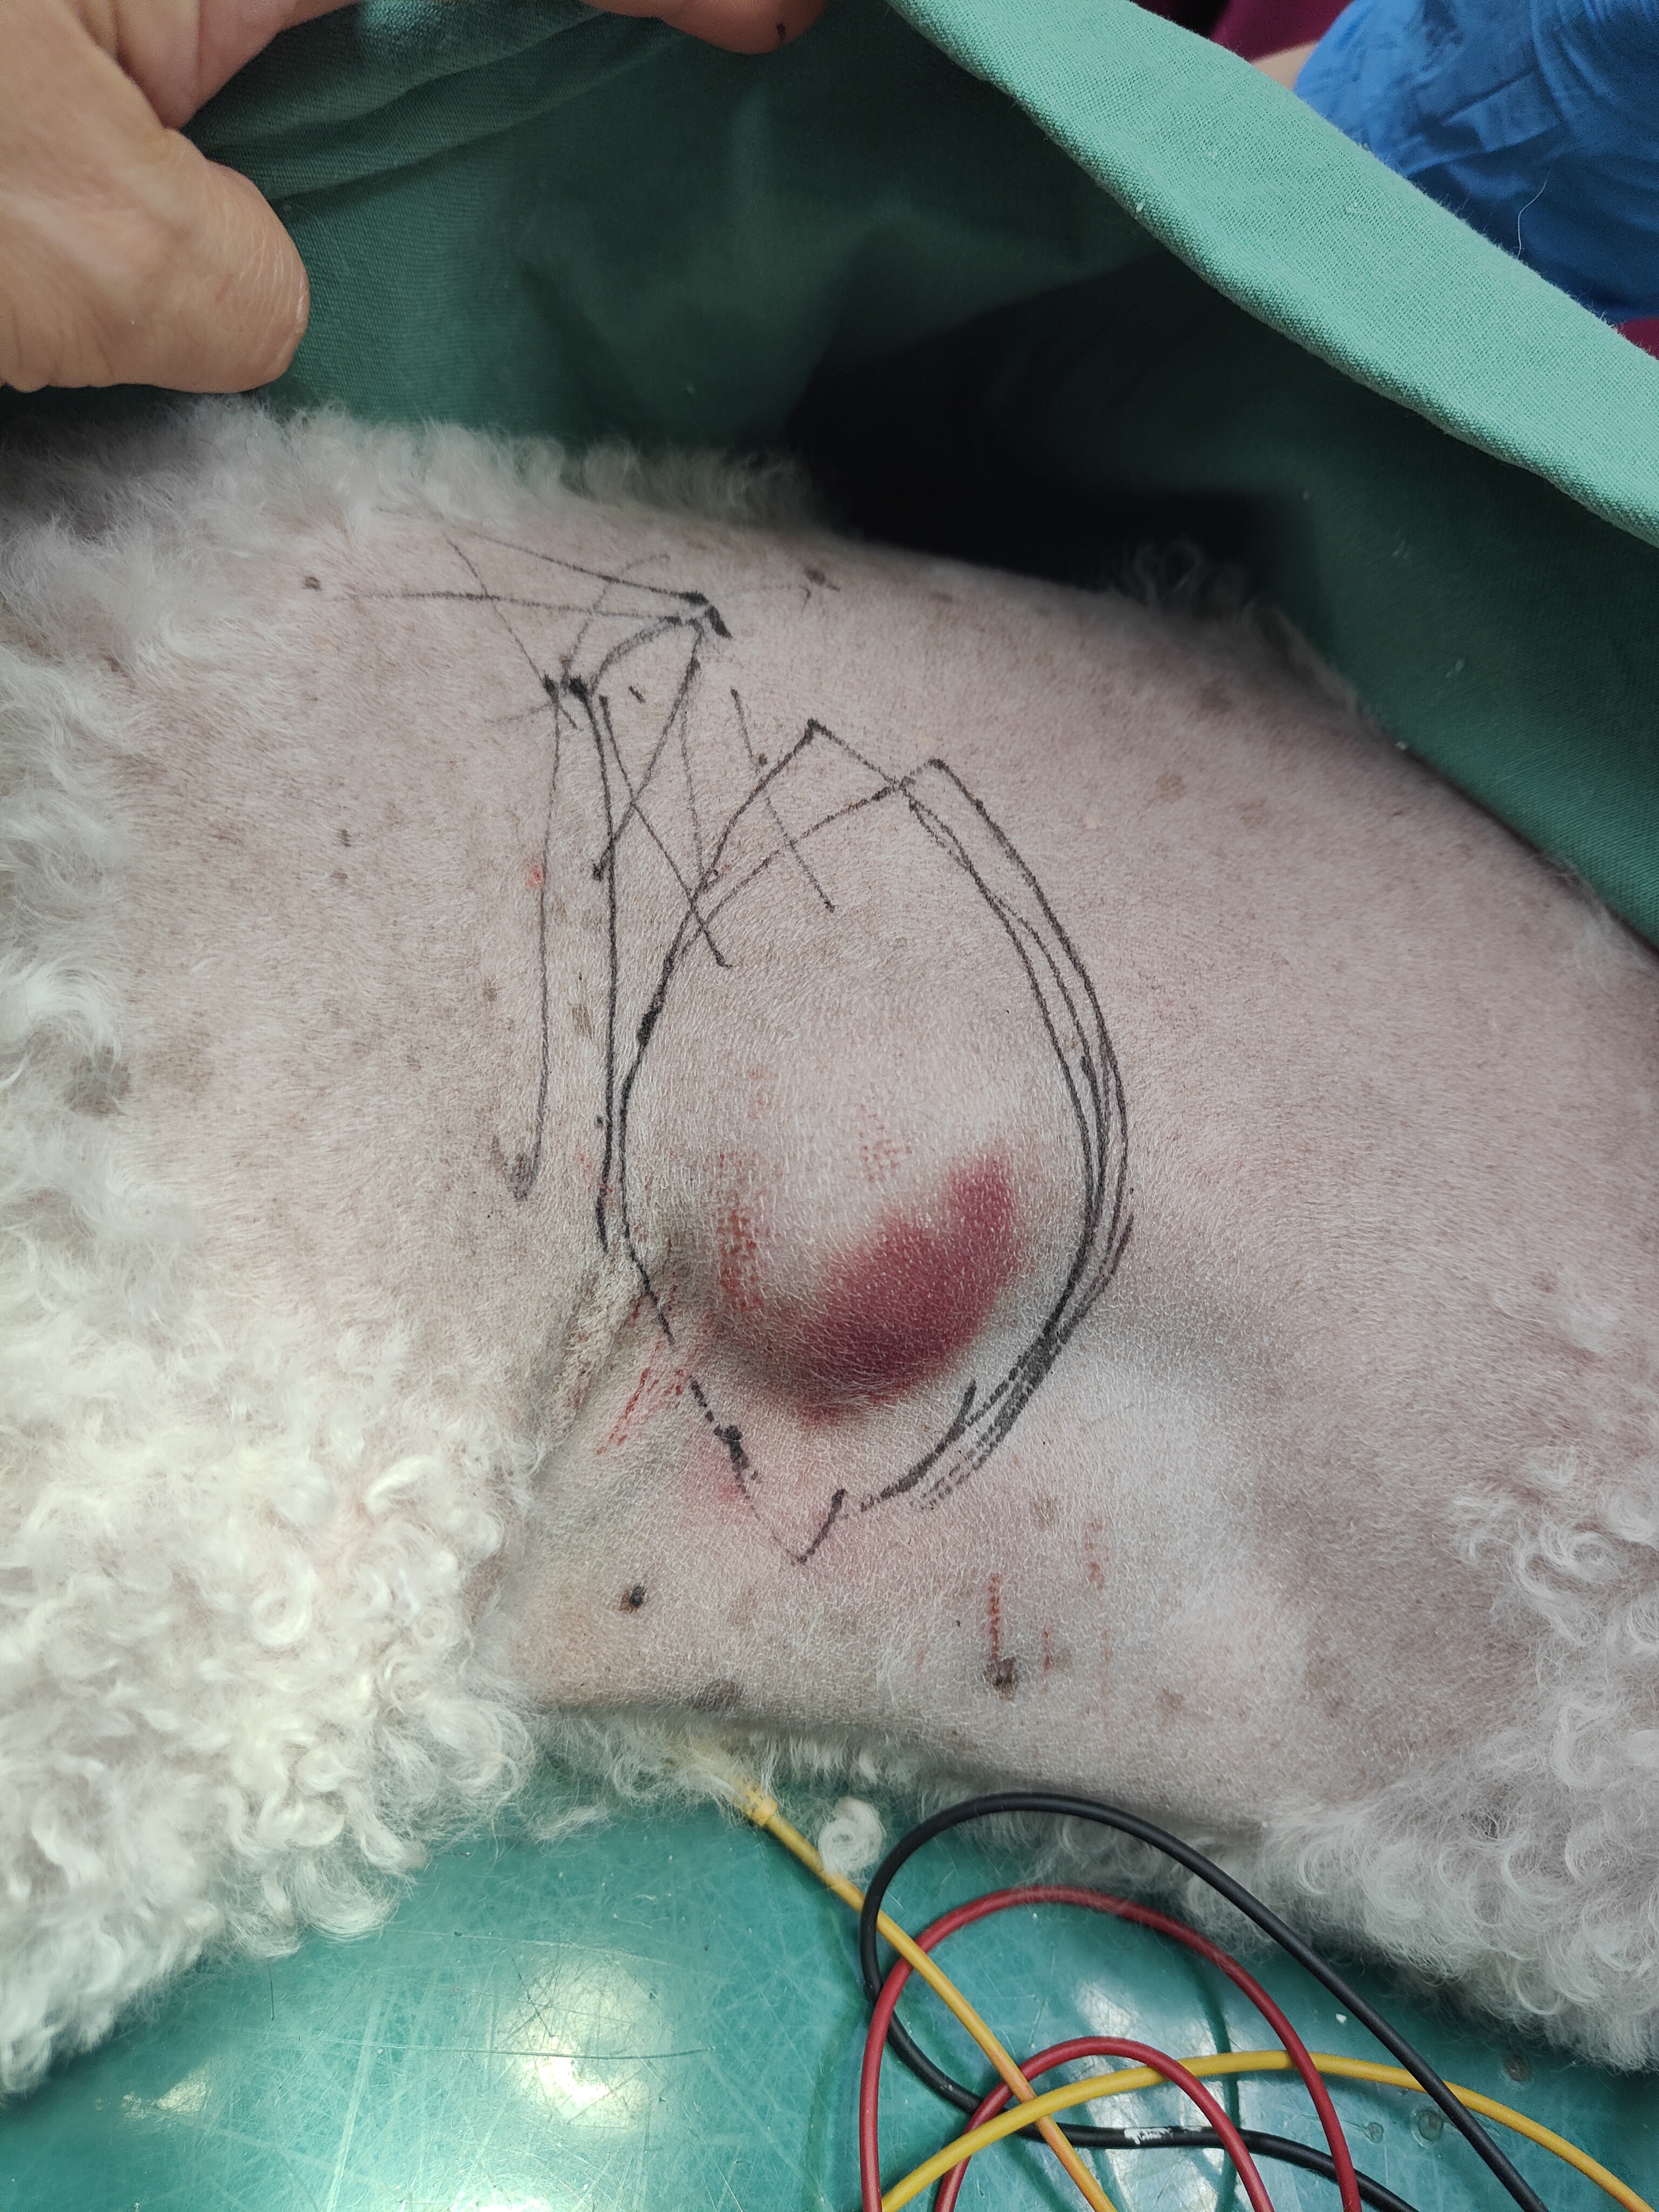

今の病院で、脂肪腫と診断されたそうですが、不思議と!内出血していましたので、一緒に手術することにしました。

血管とかを、皮膚の伸びる線を考え

切開する方法を決めて、マーキング!

皮膚の下の皮筋の走行考えて切開and縫合考え